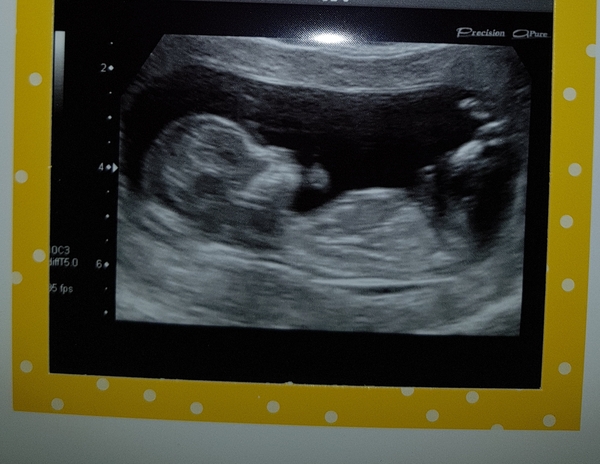

Holly257 · 11/12/2018 10:26

Had my 12 week scan yesterday and I'm right on track with a EDD of 21st of June Grin also on the what to expect when your expecting app a woman was doing the nub theory and said it looks like a little girl which would be nice as I already have 2 little boys but I suppose we won't find out until it's born Grin